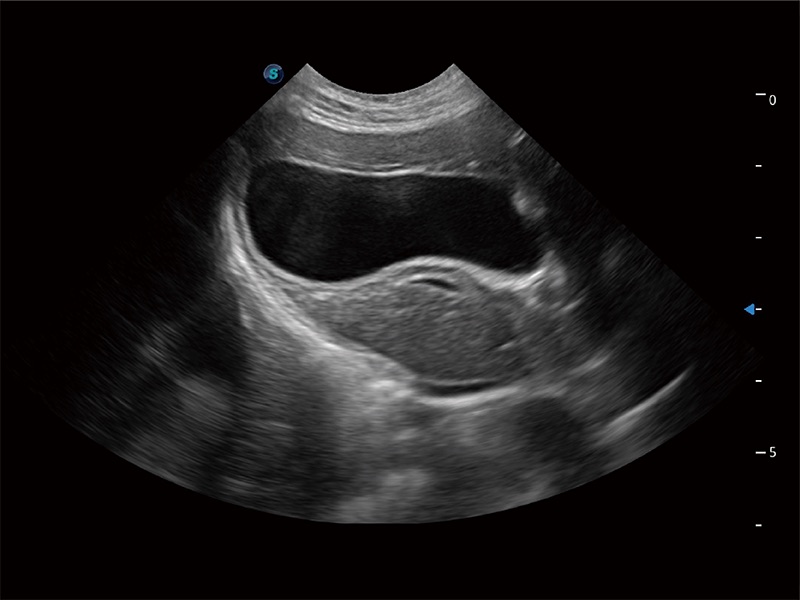

动物是人类最亲密的朋友和最值得信赖的伙伴。乐玩lewin国际也一直致力于探索动物专用的超声影像解决方案。全新推出的ProPet系列,是乐玩lewin国际在动物超声影像智能化、专业化、精准化的一次跨越式革新。动物不能用言语来表述自己的不适,通过超声影像,ProPet系列搭建了动物医生与不同物种沟通的“桥梁”,为动物医生注入了“治愈之力”。 ProPet 80 是乐玩lewin国际匠心打造的一款高端动物专用彩超,采用性能卓越的全新硬件架构,极大提升超声系统的运行效率和数据处理能力,帮助动物医生从容应对日益增多的挑战性病例和日益多样化的临床需求。

高性能和先进的临床应用工具可以为动物医生提供临床信心。ProPet 80 搭载了先进的腹部和浅表应用工具,帮助医生在日常临床实践中发挥前所未有的作用。

一键自动识别膀胱壁及自动测量膀胱容积,不受膀胱形状和大小的限制,帮助医生快速精准获得测量的数据。